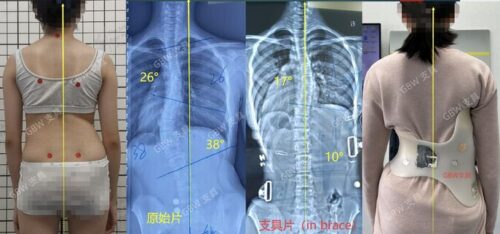

إذا كان الحبل الشوكي الضيق يحدد مدى التصحيح الجراحي، فهل يمكن أن يؤثر أيضًا على العلاجات غير الجراحية مثل التمارين والعلاج بالحزام؟ الإجابة نعم. كثير من مراكز علاج الاعوجاج تطور حاليًا برامج تهدف إلى زيادة مرونة الحبل الشوكي وتمديده تدريجيًا، ما يمنح التمارين والحزام فرصة أفضل لتحقيق نتائج ملحوظة.

العلاج غير الجراحي: استخدام أحزمة طبية مخصصة وتمارين لتقوية العمود الفقري وزيادة مرونة الحبل الشوكي.

المتابعة المستمرة: تصوير دوري بالأشعة لمراقبة الانحناء ومدى التقدم في العلاج.

أحدث التقنيات العالمية: نعتمد على تقنيات حديثة مثل أجهزة التقييم الدقيقة وأحزمة التقويم المتقدمة مثل PioBrace.